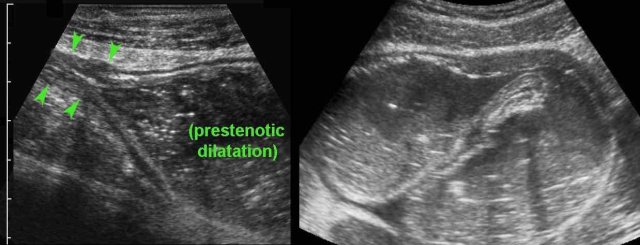

Stenosis and prestenotic dilatation

Inflammatory bowel wall thickening or the ensuing fibrotic strictures may finally result in luminal narrowing, stenosis and bowel obstruction.

The affected segment typically demonstrates dysfunctional motility.

In case of acute abdominal symptoms, US can demonstrate the presence of prestenotic dilatation and therefore proves symptomatic stenosis.

This young woman with known Crohn’s disease had intermittent colicky attacks that were never documented with imaging. She was asked to come back immediately during an attack  to undergo US

Now US demonstrated marked prestenotic dilatation proximal to a short segment of abnormal ileum (arrowheads). Higher up there was another stenotic segment.

Since there was no reaction on medical therapy, this was considered a fibrotic stenosis and this patient underwent successful surgery.

Here a fibrotic stenosis in an ileal segment.

Note the prestenotic dilatation and  absence of  peristalsis at  the level of the stricture (arrows).